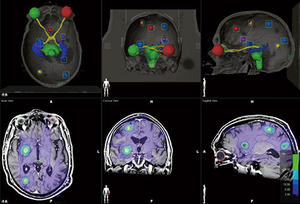

東北大学病院 ユーザビリティに優れた統合読影環境による読影業務の改善 操作性を追求した画像診断ワークステーションとレポートシステムを採用